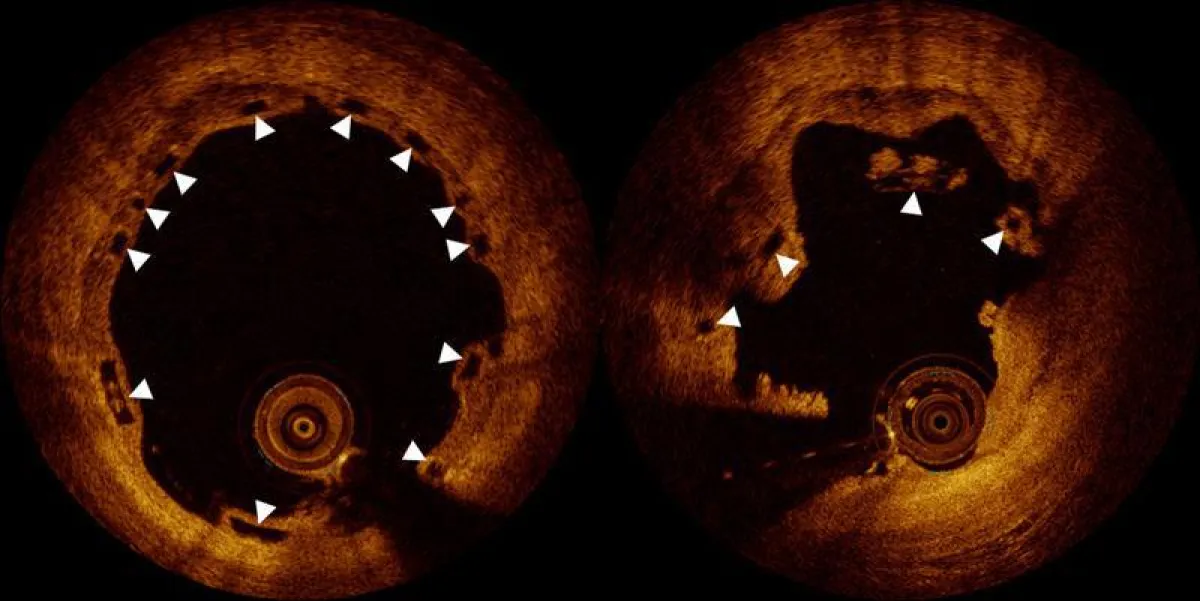

Warum Komplikationen auftraten, war zunächst unklar. Nun haben Forscher des Inselspitals unter Leitung des Kardiologen Prof. Dr. Lorenz Räber die Ursache entdeckt. Die Kardiologen des Berner Universitätsspitals hatten in Zusammenarbeit mit Universitäten aus Europa und Asien 36 Patienten und Patientinnen untersucht, die späte Bio-Stent-Verschlüsse, also über ein Jahr nach Implantation, erlitten hatten. Erst mittels optischer Kohärenztomographie, einem Bildgebungsverfahren, das nahezu mikroskopische Bilder aus dem Inneren der blockierten Gefäss liefert, wurde die Ursache sichtbar:

«Die Befunde haben uns überrascht», sagt Lorenz Räber. «Obwohl die Stents korrekt implantiert wurden, sahen wir Einbrüche des Stentgerüsts ins Innere des Gefässes.» Eigentlich macht der Stent das, wofür er konzipiert wurde: Er löst sich in einzelne Fragmente auf. «Sind diese Fragmente aber noch nicht vollständig in die Gefässwand eingewachsen, können sie im Rahmen des Auflösungsprozesses in den Blutstrom fallen. Dort führt dies zu einer gefährlichen Gerinnselbildung und damit zum Herzinfarkt.»